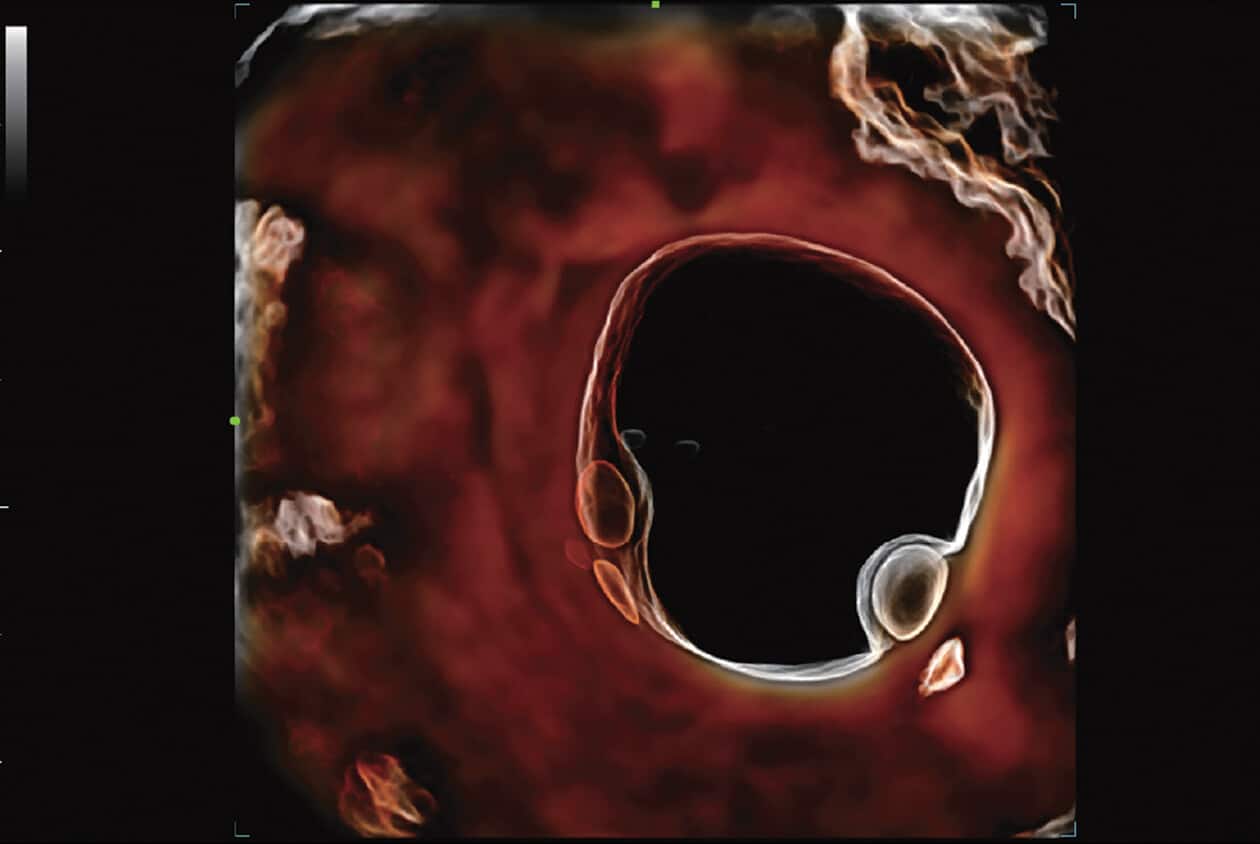

Powered by Mindray’s revolutionary ZONE Sonography (R) Technology+, the Imagyn I9 System boasts advanced ultrasound capabilities and leverages AI-inechanged technologies. The Imagyn I9 starts the process using auto clinical scenario identification, and uses automation at every point, from imaging optimization to planes scenario identification, and uses automation at every point, from imaging optimization to planes acquisition, quantification, and creating an automated workflow. The Imagyn I9 System provides a full-stack smart solution for efficient women’s health, covering wide-ranging applications from pre-pregnancy to obstetric to post-partum.